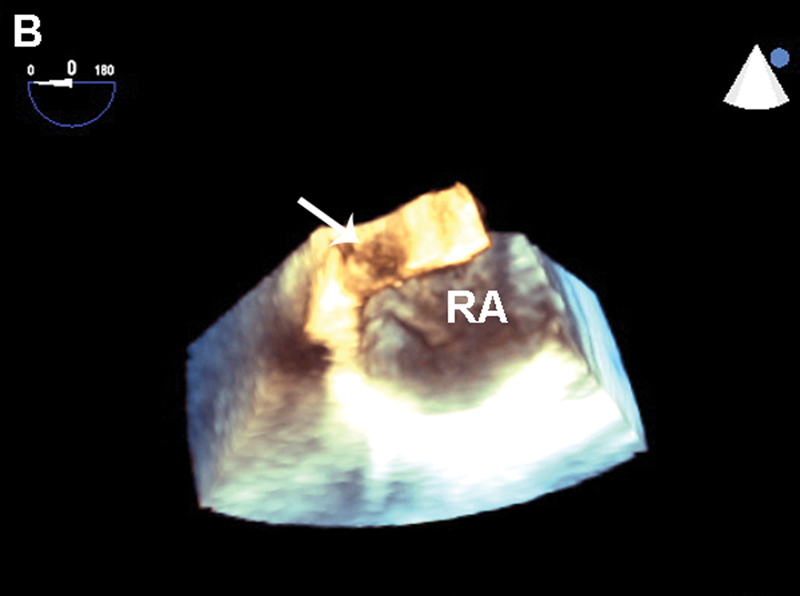

فحوصات تشخيصية لبعض امراض القلب والشرايين التاجية